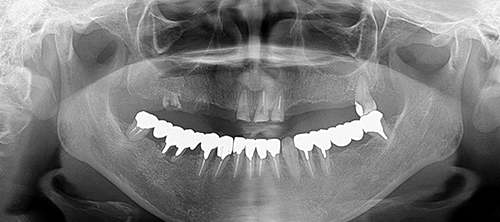

前歯が外れた(50代)インプラント・セラミック修復

年齢 53歳

性別 女性

主訴 前歯が外れた

治療内容 ・インプラント

・セラミック修復

治療期間 1年半

治療費用 430万円

治療経過 上顎は前歯以外は保存不可能と診断した

上顎の前歯も状態が万全ではないため、上顎総義歯も治療計画の1つであったが、固定式の歯を希望されたため上顎は前歯以外をインプラントにて、下顎は予後不良な奥歯を抜歯しインプラントにて咬合再構成をおこなった

現在術後5年が経過しているが不安のあった上顎前歯も問題なく機能している。

インプラントを使用することで残存歯の温存につながった症例である。

Before